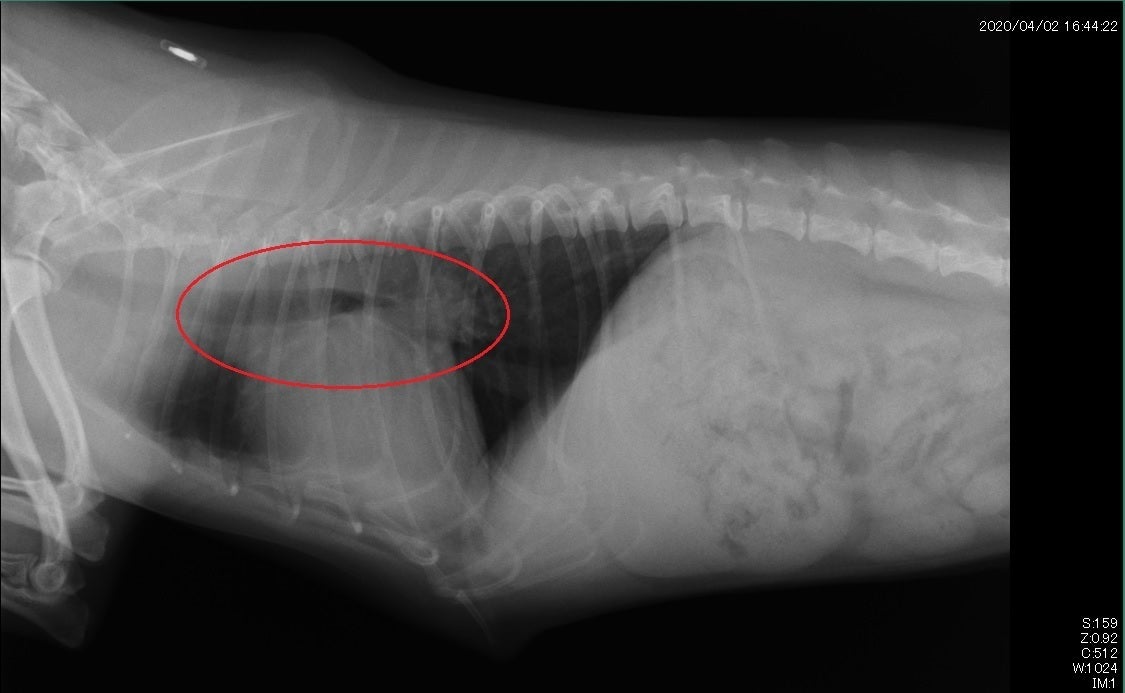

初診時。心臓の肥大がみられ気道を上へ押し上げ圧迫しています。